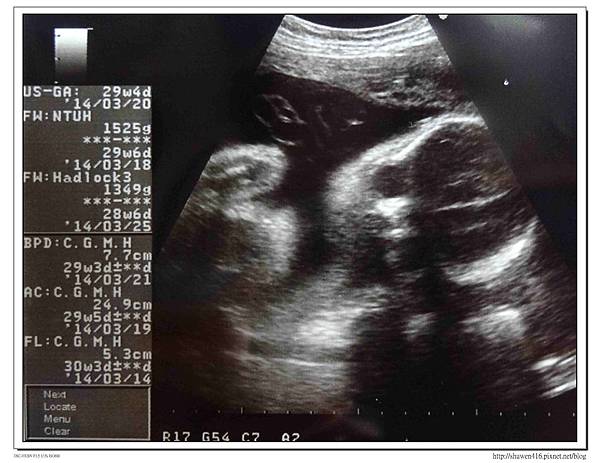

這次產檢醫生告知胎位已經轉正,難怪頻尿狀況增多,有次夜裡肋骨還被踢到有點痛,一進入診間還未照超音波,醫生說四周前產檢時是981g,讓我們來看看寶寶這次有沒有到達一千二,結果超音波結果出乎醫生預估,直接衝破一千五1525g,整整大了一週,頭圍等其他指標都超前,尤其是大腿骨更是長了好多,儼然是個長腿寶寶。